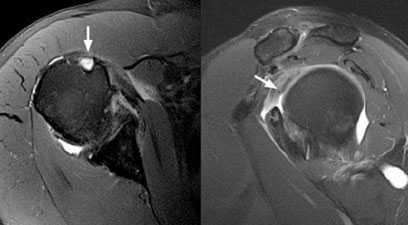

Для уточнения диагноза, определения степени повреждения подключают дополнительные методы обследования. Широко используется УЗИ, метод позволяет безошибочно определить полные разрывы. Для получения более точной информации о локализации повреждения, а также для визуализации небольших надрывов и внутрисуставных повреждений применяют МРТ.

Рис.3 МРТ-картина разрыва сухожилия длинной головки бицепса